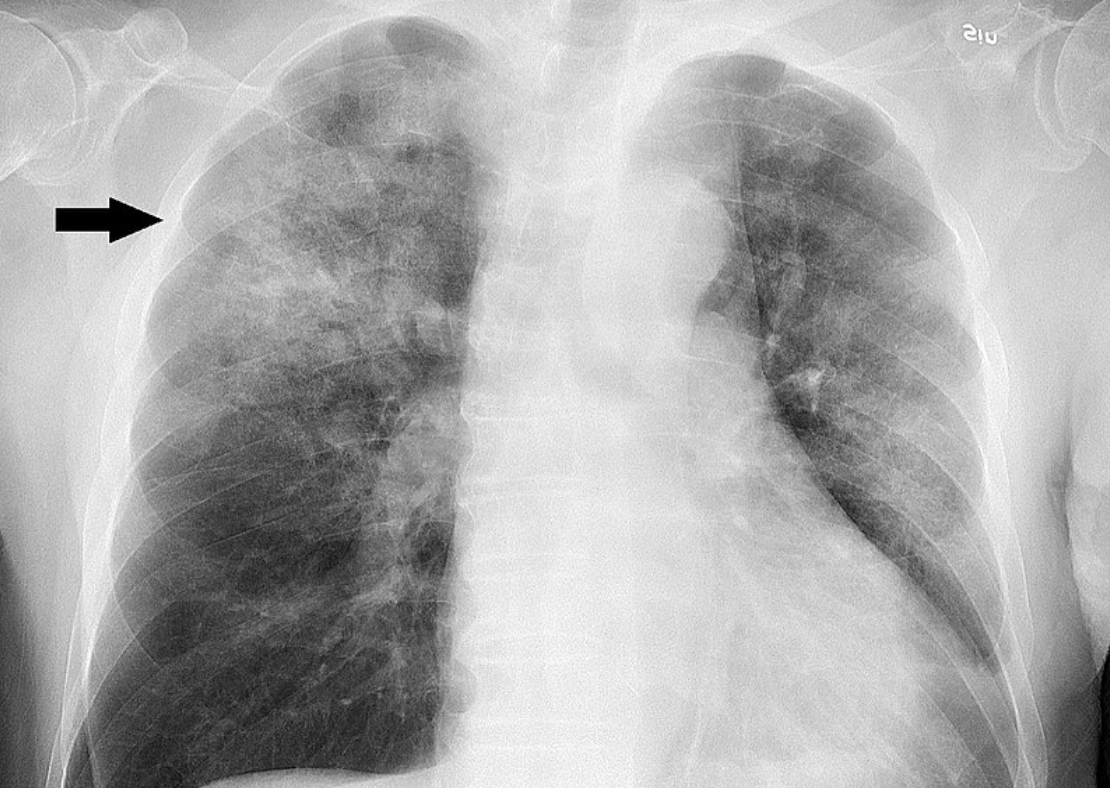

*방사선검사

4) 진단: X 선 검사, 투베르쿨린 검사, 객담배양, 늑막액배양 등

- 전형적 결핵결절, X 선 검진에서 병변, 투베르쿨린 양성